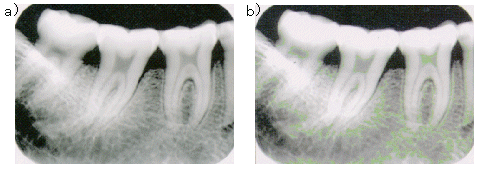

¡¡2a)¤Ï¡¢¥ª¥ê¥¸¥Ê¥ë²èÁü¤Ç¤¢¤ê¡¢½¾Íè¤Î¼Ì¿¿¥Õ¥£¥ë¥à¿ÞƱÅù¤ÎÆÃÀ¤ò¼¨¤·¤Æ¤¤¤ë¡£2b)¤Ï¼þÇÈ¿ô½èÍý¤Ë¤è¤ë¶¯Ä´½èÍý²èÌ̤Ǥ¢¤ê¡¢ÇòÀþ¡¦»õº¬Ëì¹Ð¤ä»õ²ç½¼Å¶Êª¤¬ÌÀÎÆ¤Ë¸½¤ì¡¢º¬Àí¤Î¹ü¹Å²½Áü¤Î´Ñ»¡¤â½ÐÍè¤ë¡£¼¡¤Ë¡¢¸ýÆâË¡¤ÇÆÀ¤é¤ì¤¿Âç±±»õÉô¤ÎXÀþ²èÁü¤ò¿Þ3¤Ë¼¨¤¹¡£

¿Þ3¡¡Âç±±»õÉô¤ÎXÀþ²èÁü a)¥ª¥ê¥¸¥Ê¥ë²èÁü b)ñ¿§¥«¥é¡¼¤Î¶¯Ä´²èÁü¡Ê¸¶ÏÀʸ3¤è¤ê°úÍÑ¡Ë

¡¡3a)¤Ï¡¢¥ª¥ê¥¸¥Ê¥ë²èÁü¤Ç¤¢¤ë¤¬4Çܤ˳ÈÂ礷¤Æ¤¢¤ë¡£3b)¤Ï¡¢ÆÃÄê¤Î¥°¥ì¡¼³¬Ä´Ãͤ˿§¤òÉÕ¤±¤ë¤³¤È¤Ç¡¢ÁÈ¿¥¤äƱ̩ÅÙ¤ÎÎΰè¤ò¶¯Ä´¤·¡¢Íưפ˸«Ê¬¤±¤é¤ì¤ë¤è¤¦¤Ë¤·¤¿²èÁü¤Ç¤¢¤ë¡£